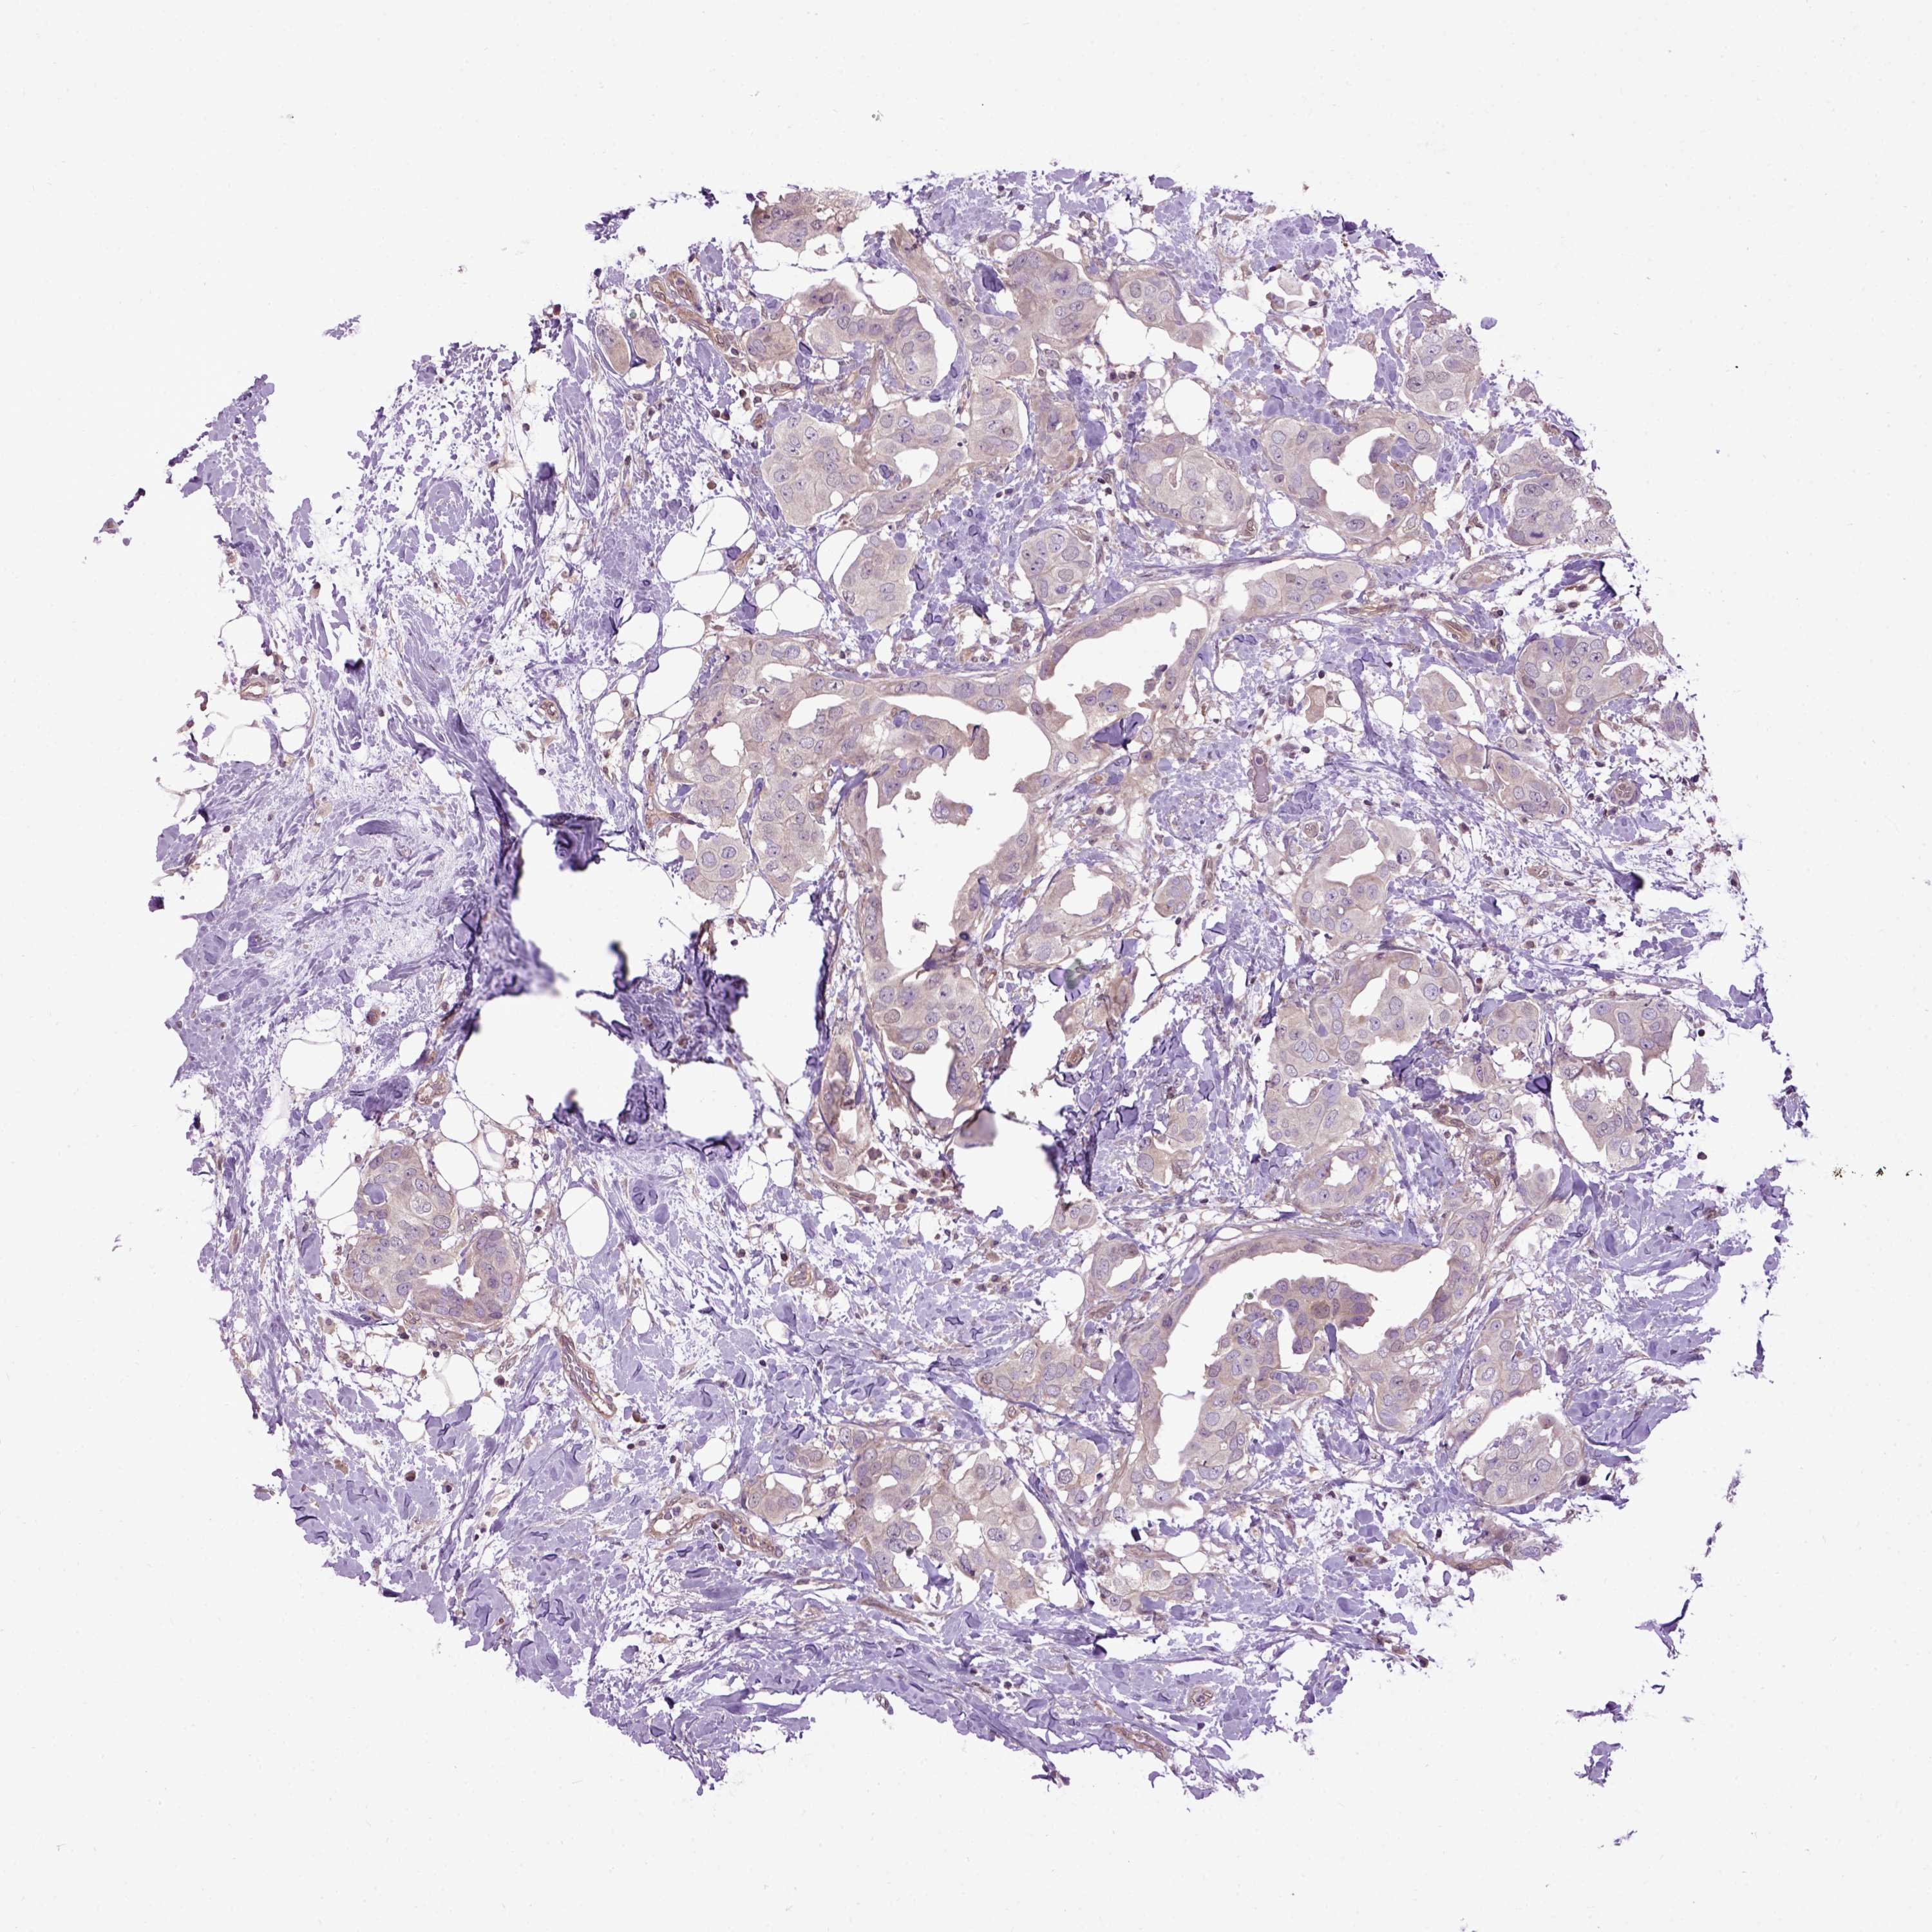

CANCER BREAST CANCER Show tissue menu

BRCA TCGA BRCA VALIDATION PROTEIN EXPRESSION